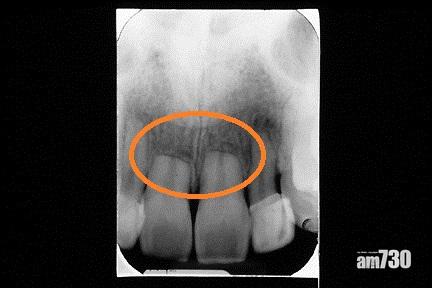

矯齒治療後門牙有牙腳收縮現象(此為嚴重收縮病例)。